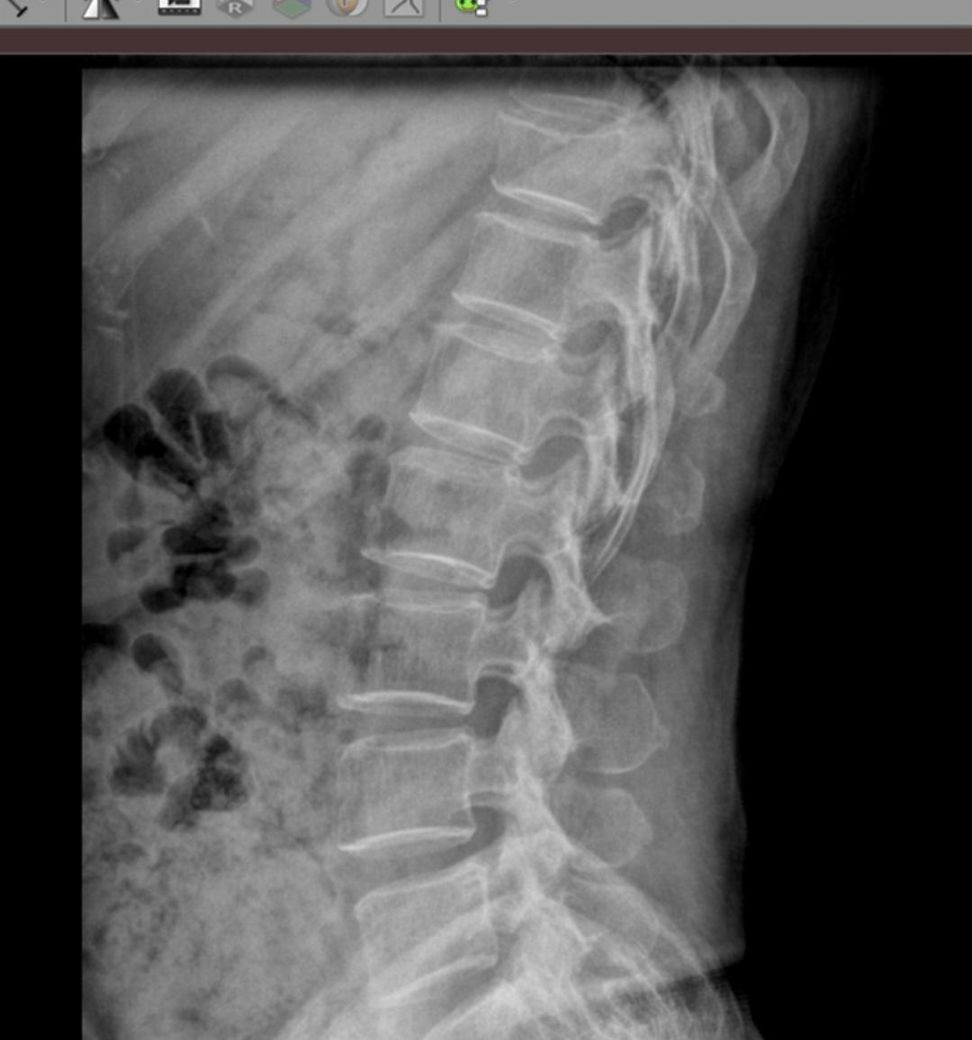

어머니가 넘어졌는데 흉추 12번 압박골절 맞을까요.?

어머니께서 넘어져서 병원 두군데 갔는데 한 곳은 압박 골절 이야기 해주셨는데 다른 곳은 압박골절 진단이 안나왔습니다

흉추 12번 부분 압박 골절 맞을까요? 사진확인 한번만 브탁 드립니다

엑스레이사진상으로는 정확한 상태를 확인하기는 어려울 것 같습니다. 연속성이 약간 무너져 있는 것으로 보이긴 하지만 정확한 상태 파악을 위해서는 MRI검사를 받아보시는게 좋을 것으로 생각되며 영상 검사를 추가하거나 전문 척추 병원에 방문하시어 판독을 받아보시는게 좋을 것으로 생각됩니다.

사진상에서는 크게 특이사항이 확인되지 않지만, 압박골절이 의심되는 경우에는 며칠 더 경과를 살펴보시고 다시 진료와 검사를 받아보시는 것을 추천드립니다.

척추를 다 보여주셔야 몇번 척추인지를 알 수 있습니다.

아래 표시한 척추는 확실히 골절이 맞습니다. 하지만, 예전에 부러진건지 이번에 부러진건지는 명확하지 않습니다.

그런데 해당 척추 밑으로 보이는것만 6개 척추가 있음으로 이놈이 12번 흉추는 아니라는 이야기라서 어느 척추가 궁금하신건지 표시를 부탁드립니다.

• 올리신 사진을 보았을 때에 12번 흉추는 딱히 압박골절을 의심할 정도의 소견으로 보이지 않습니다. 가능성이 있다면 그보다 윗쪽에 있는 10번 흉추가 압박골절의 가능성이 더 높아 보이긴 하지만, 해당 부위 또한 아주 명확한 압박골절 소견이라고 판단을 내리기는 어렵겠습니다.